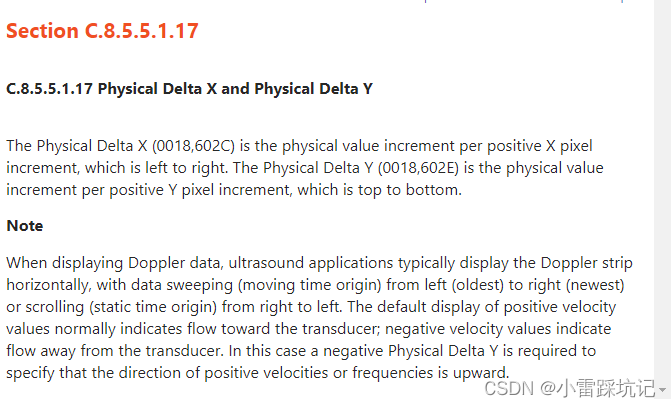

这段的解释,我理解出来的意思:us采集的时候,(就是做超声),拿着探测头在腹部左右扫描. 注意一下ct设备采集的时候,参照点是世界坐标系,但是这个做超声扫的时候,只是扫腹部平面可以看成是二维的面 ,这个时候这两个值x,y其实就相当于从左到右,从上到下的一个物理上的间距,也可以看成是物理上的一个缩放比.(非医疗人员,解释可能不太准确,如果有专业人士看见了,麻烦指导一下).

特别注意一下这个 PhysicalDeltaX ,PhysicalDeltaY 值需要同时 *10,才是最终像素